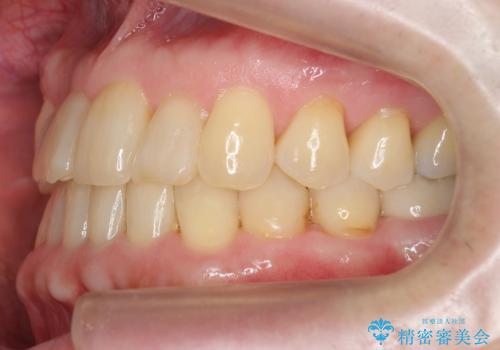

矯正治療後、右下のインレーブリッジおよび左下の銀歯のやりかえを行なっています。

右上の八重歯は、右上の奥歯を矯正用ミニスクリューを用いて遠心移動を行い解消しました。

下の前歯はIPR(エナメル質を薄く削り歯を小さくする処置)を行なっています。